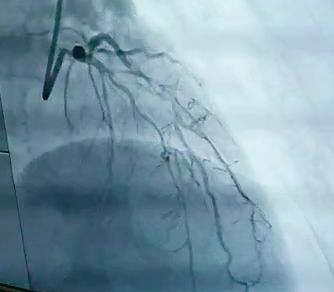

西医应对糖尿病的方法还包括运动治疗和饮食治疗。再举一个病例。曾有一位北京的糖尿病患者(同时有高血压、高血脂),长期暴走锻炼不吃药,最终的结果是差一点丢了性命。医生在抢救中才发现了问题所在。这名患者长期锻炼身体打赢了血压战,也赢了血脂战,但却在糖尿病这一项上阴沟里翻了船。等到造影一做,因为没有控制住血糖,前降支近段100%堵塞,其他几支重要血管各有不同程度的弥漫性狭窄,如果正常的心脏血管打10分,他这颗心脏的血管情况可能3分都不到。